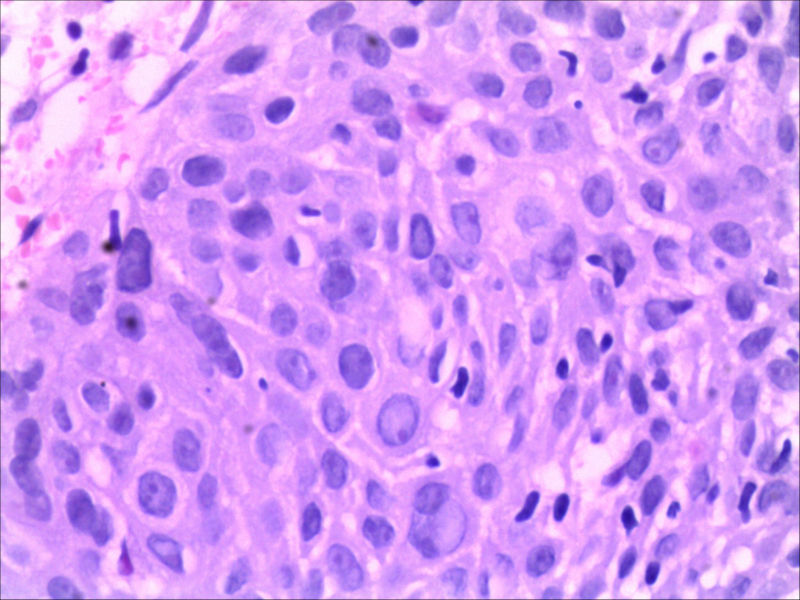

食管活检男64岁食管粗糙

• 食管活检男64岁食管粗糙图4

图4

高级别上皮内瘤变,取材表浅,不排除高分化鳞癌,请结合临床建议必要时再取活检

同意,本例仅出现食管黏膜粗糙,如果没有较大肿块或溃疡,也有可能就是个高度上皮内瘤变或早期食管癌。因此可做超声内镜,如果可能,做大黏膜切除治疗。